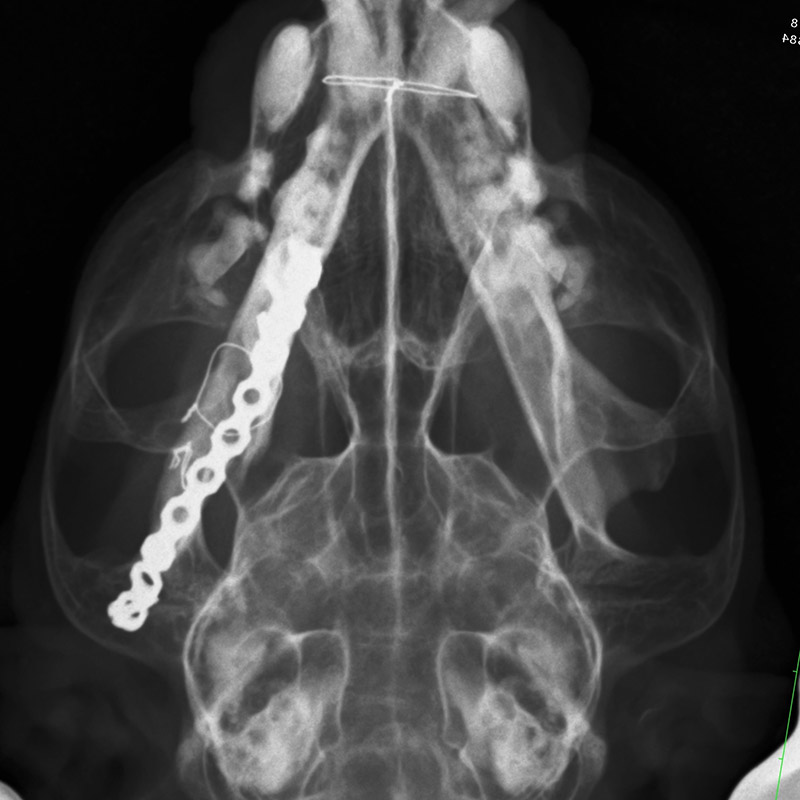

下顎骨骨折

雑種猫(14歳)

犬に咬まれた

手術前

手術後

CT正面